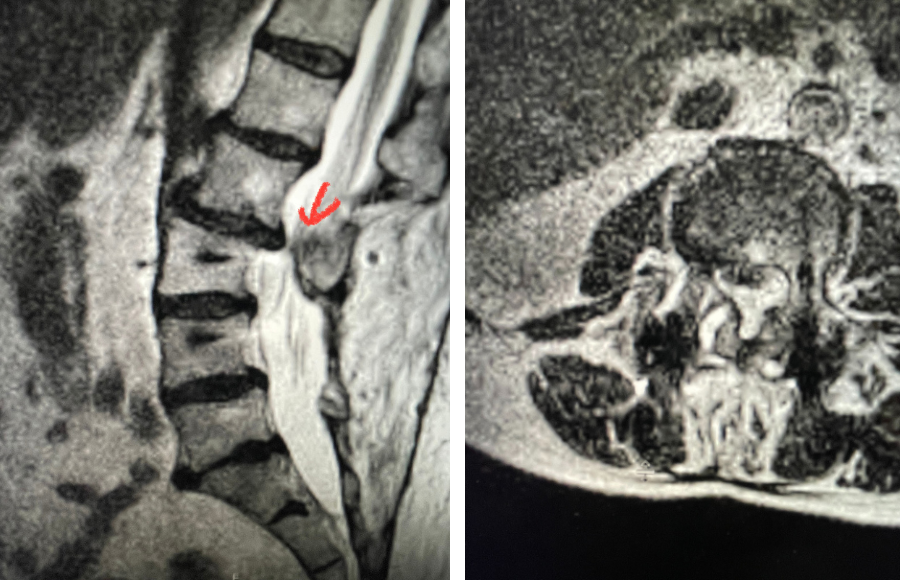

Fig 4: Sagittal and axial T2-weighted lumbar MRI images demonstrating severe next segment degeneration and stenosis at L2-3 above prior L3-5 fusion. Note retrolisthesis and significant facet arthropathy at L2-3 (red arrow).

Here is a dramatic example of a patient who had prior laminectomy and fusion surgery four years earlier, and now presents with low back pain with severe burning pain in her right lower extremity pain. She did not respond to epidural steroids. She had a prior L3-S1 laminectomy, and an L3-5 instrumented fusion. A current MRI (Fig 4) demonstrated severe L2-3 next segment stenosis due the development of massively hypertrophied or enlarged L2-3 joint complexes. There was also a grade 1 retrolisthesis of L2 on L3 with a large anterior disc osteophyte complex. The configuration of the stenosis was worse in the right lateral recess secondary to the anterior osteophyte and more right-sided facet compression of the thecal sac, correlating with the patient’s right-sided symptoms. When the anatomy correlates with the patient’s symptoms that is the best set up for success. It was decided to offer a revision surgery to the patient, who agreed.